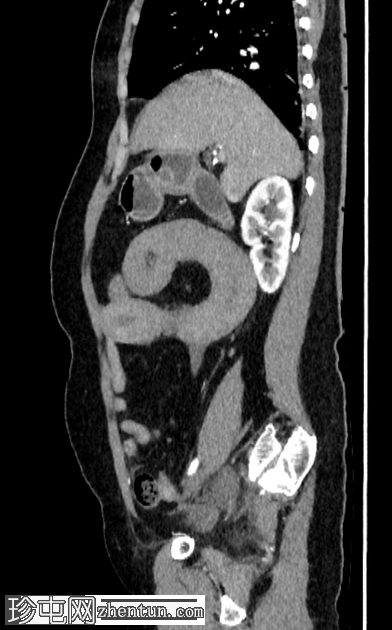

轴位增强扫描

动脉期

空肠(长段,60 cm)肠壁弥漫性节段性增厚。肠壁呈高密度影,平扫CT值约为56 HU,并可见强化。

可见肠系膜水肿和血管充血,以及少量腹水。

肠系膜上动脉和静脉通畅,未见血栓。

影像学表现最提示黏膜下出血。